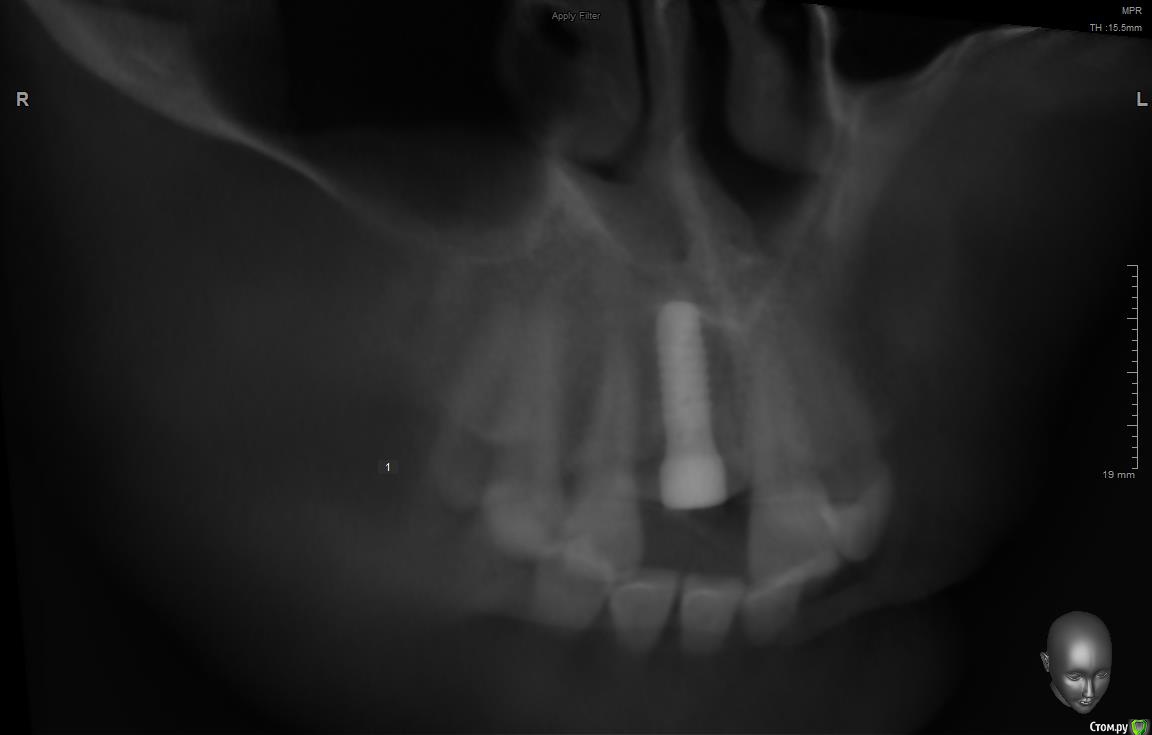

jm3300 Опубликовано 11 сентября, 2019 Поделиться Опубликовано 11 сентября, 2019 Имплант( система, производитель) не известен, формирователи подобные не видел, шестигранные отвертки не подходят( на формике отверстие под четырехгранник). Данных на имплант у пациента нет. В клинике, где ставили, якобы, не помнят что ставили. Может кто встречался с ними? Ссылка на комментарий

АнтонТЛТ Опубликовано 11 сентября, 2019 Поделиться Опубликовано 11 сентября, 2019 (изменено) Что за мода выкладывать срезы Кт, на которых всё фонит. Лучше уж прицельный снимок. Возможно это конмет, у них квадратный шлиц. Изменено 11 сентября, 2019 пользователем АнтонТЛТ 2 Ссылка на комментарий

dr Alexandr Опубликовано 14 сентября, 2019 Поделиться Опубликовано 14 сентября, 2019 Похож на Конмет, у этой системы своя протетика и ортопедический набор! Отвёртка у них 6 гр только меньше, нужно попробовать выкрутить фдм, там понятнее будет 1 Ссылка на комментарий